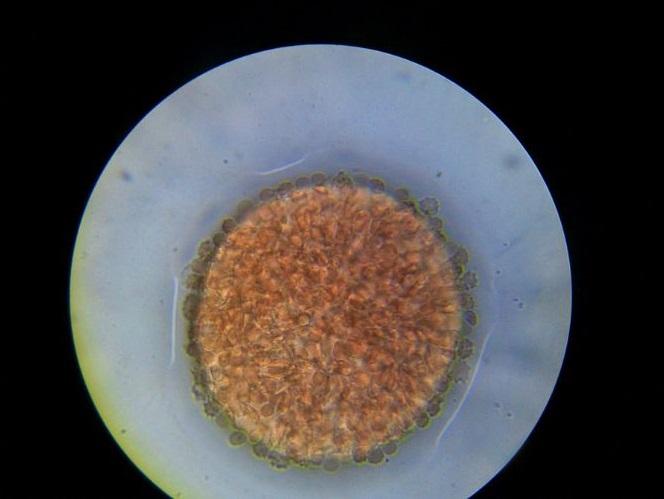

El proeritroblasto es una célula grande, su tamaño es 10 veces mayor al del eritrocito maduro. Esta célula se caracteriza por presentar un núcleo redondo, y en algunas ocasiones es posible observar 2 o más nucleolos bien delimitados. El citoplasma tiene gran afinidad por los colorantes básicos y es teñido intensamente por este.

Con tinción de hematoxilina-eosina, el citoplasma es de color azul intenso. El proeritroblasto conserva la capacidad de dividirse por mitosis que posee su antecesor y la mantiene hasta la etapa de normoblasto basófilo.

El proeritroblasto es una célula grande, su tamaño es 10 veces mayor al del eritrocito maduro. Esta célula se caracteriza por presentar un núcleo redondo y algunas veces es posible observar de 2 o más nucleolos bien delimitados. El citoplasma tiene gran afinidad por los colorantes básicos y se tiñe intensamente.

El citoplasma de los proeritroblastos es característicamente basófilo. Por tanto, con cualquiera de estas tinciones el color que tomará será azul violáceo intenso. Mientras que el núcleo se colorea de púrpura.